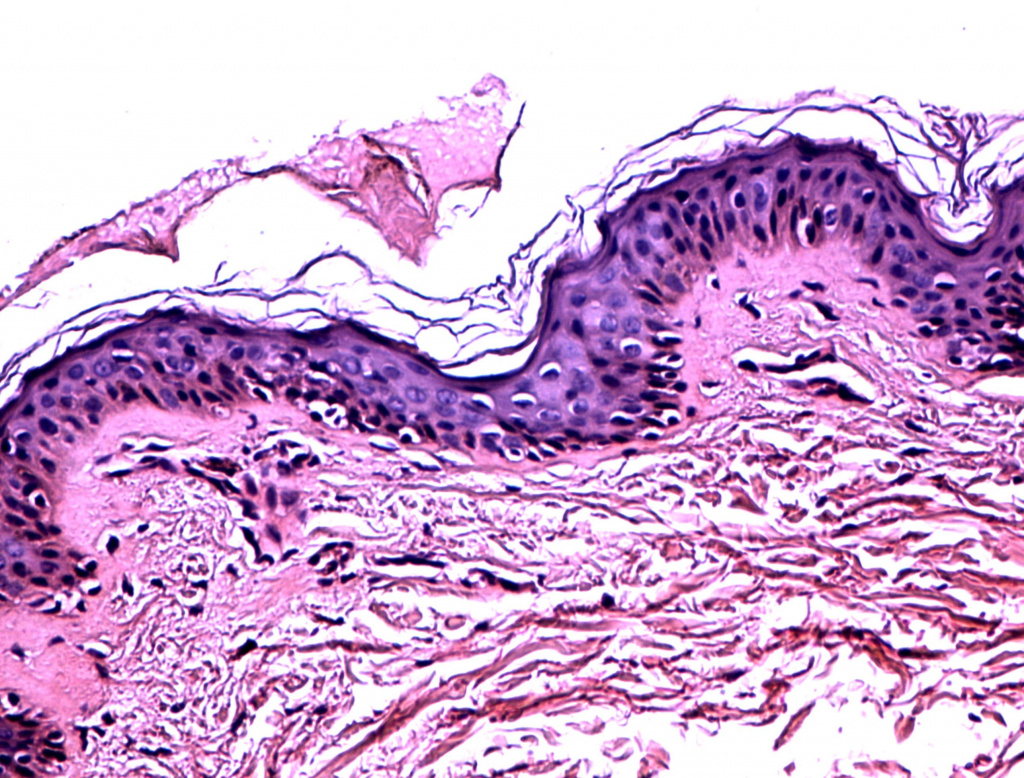

Уже после первой процедуры отмечается выравнивание цвета лица и увеличение тургора кожи (рис. 1-2). Процедуры переносятся очень комфортно, небольшая гиперемия в некоторых случаях держится до 30 минут. По результатам 3D-сканирования уменьшилась выраженность мелких морщин вокруг глаз уже через 6 дней после первой процедуры (рис. 1-6). Также проведено гистологическое исследование сразу после процедуры (рис. 7) (фрагмент «тонкой» кожи: единичными лейкоцитами в толще эпидермиса и на его поверхности, ядра клеток эпидермиса и их цитоплазма на данном участке набухшие, сосочки дермы несколько сглажены, рыхлая волокнистая соединительная ткань сосочкового слоя дермы отечна), на третий день (рис. 8) (отмечается уменьшение количества набухших ядер в эпидермисе, мелкоочаговое кровоизлияние в сетчатом слое дермы с перифокальной сосудистой реакцией и слабовыраженным отеком сетчатого слоя дермы) и спустя 20 дней после процедуры (рис. 9) (В представленном фрагменте кожи заметна умеренная пролиферация клеток эпидермиса и дермы. Отмечается уплотнение коллагеновых волокон сетчатой дермы. Патологических изменений в эпидермисе, дерме, придатках кожи не обнаружено). Также наблюдаются изменения показателей влажности, пигментации и эластичности кожи (рис. 10-11).

Гистология через 3 дня после процедуры HELEO4

Рис. 8. Гистология через 3 дня после процедуры HELEO4™